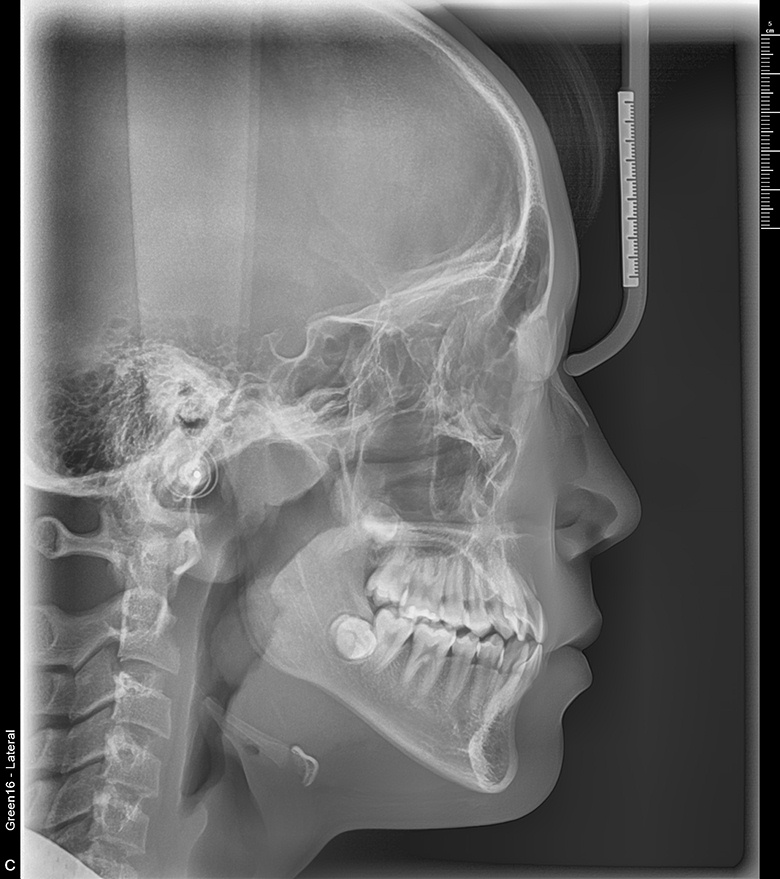

치료 전 사진입니다.